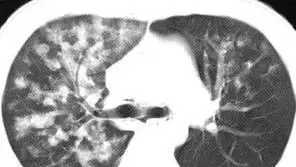

肺部磨玻璃影也是一个影像学上的概念,它指的是肺组织密度轻度升高,呈现磨砂玻璃样的改变,在磨玻璃病灶的内部,一般是可以看到血管纹理和支气管影像的。磨玻璃影不仅仅表现为结节,它也可以表现肺部弥漫性的改变,呈片状或者斑片状改变。

那么人体肺组织内为什么会出现磨玻璃影,磨玻璃影的本质其实是肺间质改变。在肺部,可以引起磨玻璃影改变的疾病是非常多的,比如说肺水肿、各类肺炎、病毒性肺炎、急性间质性肺炎、病毒肺炎等,都是可能表现为肺部磨玻璃影的。

当然,早期的肺癌也是可以表现为磨玻璃影,不过早期的肺癌形态一般都是比较规则的(表现为类圆形),所以一般我们又称之为磨玻璃结节。

典型的肺部磨玻璃结节